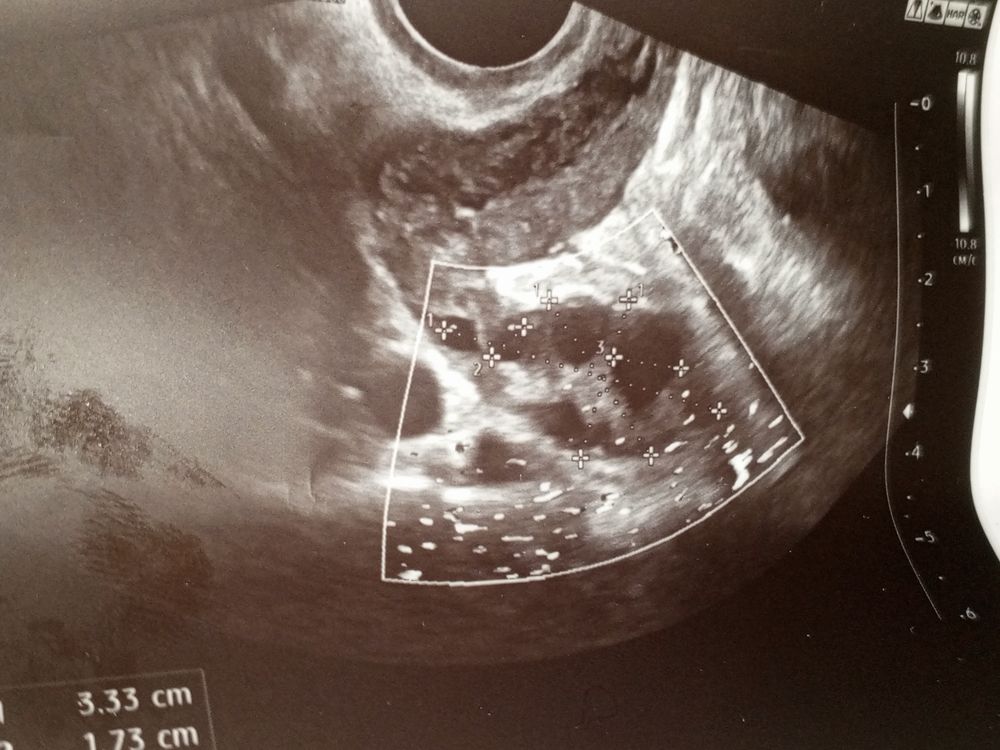

УЗИНу подскажите, на фото же только фолликулы, нет жёлтого тела?

Я хоть часто и делаю УЗИ но некоторые моменты не понимаю